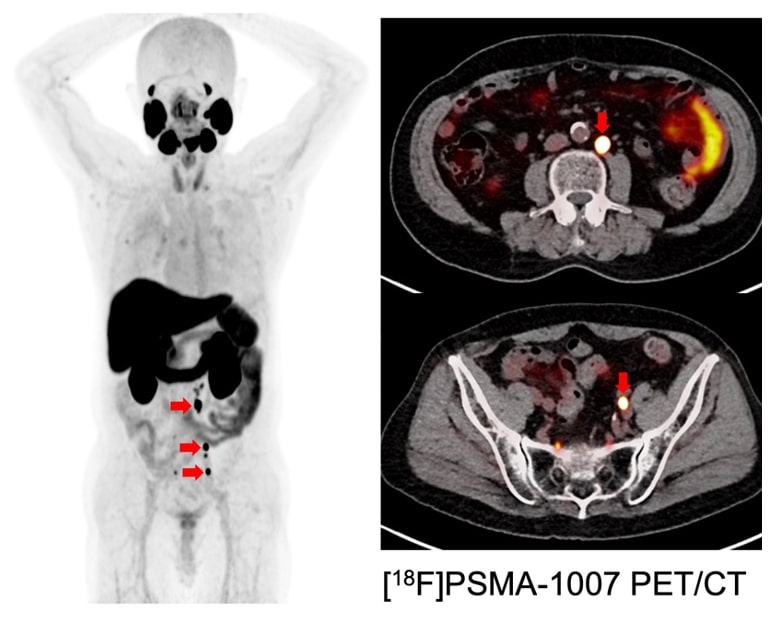

医師は、 PSMA PET スキャンなどの画像診断検査を使用して、前立腺がんが体の他の部分に転移しているかどうかを調べます。

PSMA PET スキャン中、技術者は放射性トレーサーを含む特別な色素を静脈に注入します。トレーサーは、前立腺特異的膜抗原 (PSMA) と呼ばれるタンパク質に結合します。 PSMA は前立腺がん細胞に大量に含まれています。

あなたがマシンに横たわっている間、特別なカメラがあなたの体の画像を作成します。放射性トレーサーにより、医師はスキャン中に前立腺がん細胞の位置を確認しやすくなります。